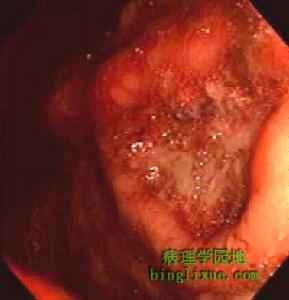

2.內鏡檢查內鏡下胃黏膜色澤發黃,常伴有散在性白斑,黏膜皺襞可表現紅、腫、肥大。但這些表現均缺乏特異性。結腸鏡下常觀察到與潰瘍性結腸炎類似的表現,即黏膜水腫、糜爛、瀰漫性黏膜發紅及潰瘍。有的還可以出現息肉樣改變。下消化道出現梗阻症狀時,在乙狀結腸有時可以看到與BorrmannⅢ型癌難以鑑別的隆起性潰瘍。